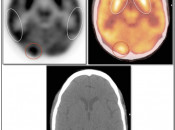

Brain

As the brain fully relies on glucose metabolism, it demonstrates rather diffuse intense uptake of FDG. In fact, its metabolic activity is so intense, that most PET reading software programs will require the reader to manually decrease its intensity to evaluate the brain for potential lesions.

Familiarity with the normal symmetric uptake of FDG in the brain will help the reader identify primary brain tumors and metastatic lesions.

Areas of normal relative increased uptake include the grey matter, basal ganglia, frontal eye fields, posterior cingulate gyrus and visual cortex. Symmetry of uptake should be preserved.